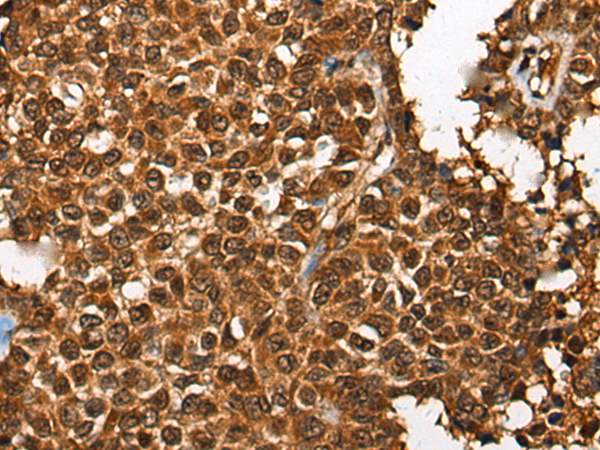

IHC positive control:

Human liver cancer and human ovarian cancer

IHC Recommend dilution:

30-150